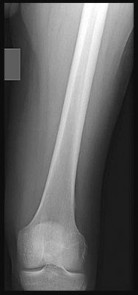

Question 5:

A 22-year-old collegiate football player sustains a twisting injury to his knee during a tackle. Radiographs reveal an avulsion fracture of the lateral aspect of the proximal tibia, just distal to the articular surface (a Segond fracture). Which ligamentous injury is most strongly associated with this pathognomonic finding?

Options:

- Posterior cruciate ligament (PCL) tear

- Medial collateral ligament (MCL) tear

- Lateral collateral ligament (LCL) tear

- Anterior cruciate ligament (ACL) tear

- Medial patellofemoral ligament (MPFL) tear

Correct Answer: Anterior cruciate ligament (ACL) tear

Explanation:

A Segond fracture is an avulsion fracture of the anterolateral capsule and the anterolateral ligament (ALL) complex from the lateral tibial plateau. It is considered pathognomonic for an anterior cruciate ligament (ACL) tear. It typically occurs via an internal rotation and varus stress mechanism.